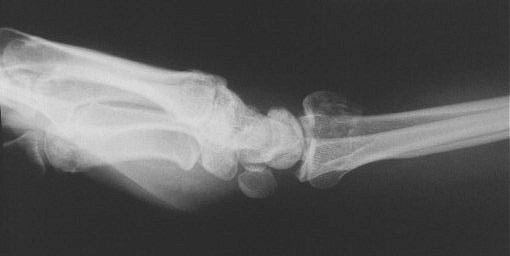

Clinical Example: Distraction plate fixation of distal radius fracture

A tricky case, for the patient previously had a large skin graft over the dorsal metacarpus / wrist / forearm. Incisions are marked here just before the plate was removed.

distal radius fracture

distraction plate